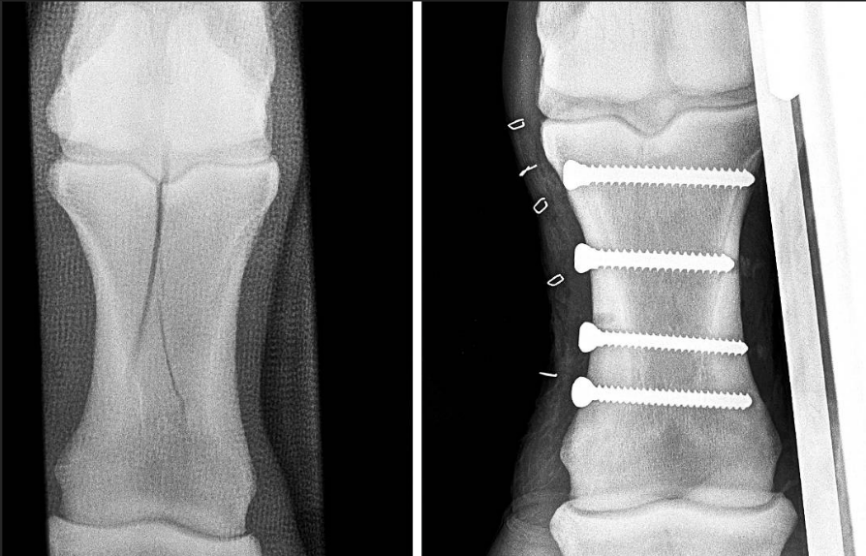

成年马的体重往往超过半吨,现有的内固定方式,很难在承受如此巨大负荷和应力的同时,提供骨折愈合所需的稳定性。

马匹骨折后,通过钢钉固定骨碎片

因此,骨折手术的本质是在帮助断端复位并维持稳定的状态——无论是采用内固定(如钢板、钢钉)还是外固定(如石膏、夹板),目的都是为了创造一个稳定的愈合环境。